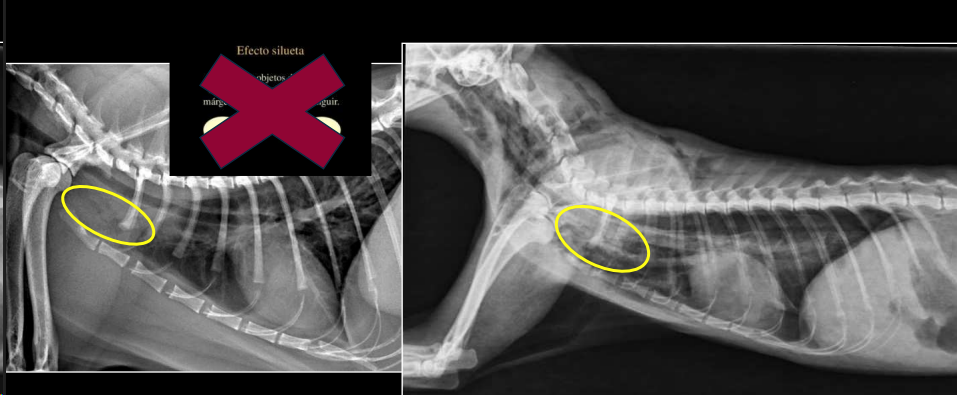

Efecto silhueta: cuando dos objetos de la misma densidad están en contacto, sus margenes no se pueden distinguir. No los distinguimos, los valoramos en grupo, buscamos cambios de tamaño, opacidad o de tamaño

Hiliares/Perihiliares: alteraciones esofágicas, tumor base cardiaca, linfoadenopatía traqueobronquial, masa tiroidea ectópica.

Masa de opacidad tejido blando que desplaza la traquea y la bifurcación bronquial.

Puede ser por los nodulos parabronquiales, esofagico o por masa en el pulmón